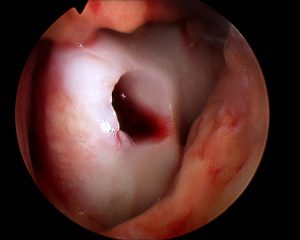

• Die Transplantate werden im Pressfit-Verfahren eingesetzt.

• Impaktierung

• Tiefenbestimmung

• Länge etwa 15 mm

• Cave: Geometrie, tiefe des Defektes bzw. Bone bruises